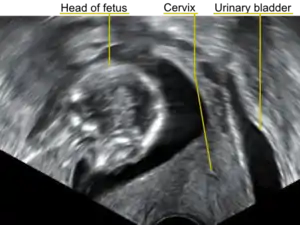

In a pregnant woman who is entering her second trimester, the combination of urinary difficulties and pelvic pain may alert the physician to consider uterine incarceration as a possibility. On physical examination, the cervix is pushed up and anterior, and the pelvis entirely filled by the soft mass of the body of the pregnant uterus. Sonography may indicate the retroverted position of the uterus, check on the viability of the fetus, and demonstrate the location of the bladder being pushed cranially and unable to be emptied.[4] Also magnetic resonance imaging has been found to be helpful in the diagnosis of the condition.[4][5]